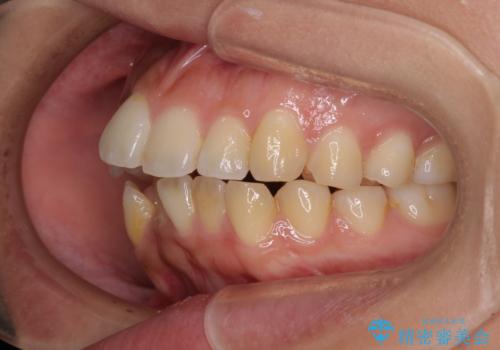

八重歯と上顎前突 ワイヤー装置での抜歯矯正

- 八重歯と、上下前歯が接触しないくらい前突した前歯を気にして来院された患者様です。

奥歯の噛み合わせは正常に近い状態でしたが、右上の奥歯に突起があったり、上下前歯が非接触であったりしていたため、補助装置を使用して上顎前歯を積極的に引っ込めるように計画しました。

口元の突出感を改善するために上下左右の小臼歯4本を抜歯し、ワイヤー装置によりデコボコを解消しながら口元の突出感も改善していくこととしました。

上下の前歯が接触する仕上がりとなったので、横顔の印象が大幅に改善されました。